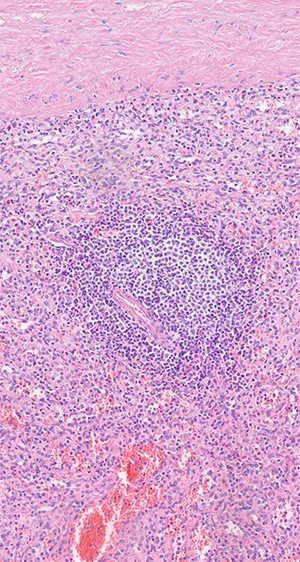

was located in the left upper quadrant of the abdomen, nearly adherent to the stomach and a moderate variceal conglomeration in the fundus of the stomach (Fig. 2). Liver cirrhosis or portal vein occlusion and other inflammatory or malignant diseases could be excluded from CT imaging. In addition, a CT scan was able to show clearly that the arterial blood supply of the accessory spleen is derived from the short gastric arteries. Splenic artery and vein could not be delineated. The patient was subsequently presented to our Department of Visceral Surgery. We decided to perform laparoscopic accessory splenectomy to relief the regional hypertension of the short gastric veins. In the operation room, the patient was positioned in right semi-decubitus position. One 12 mm Trocar, two 11 mm Trocars and on 5 mm Trocar were inserted in the left upper quadrant. The accessory spleen was extremely adherent to the diaphragm and retroperitoneal tissue (Fig. 3). After transection of the short gastric vessels with the vessel sealer (Ligasure™, Medtronic, Germany), the spleen was mobilized and removed (Fig. 4). Patient’s postoperative course was completely uneventful, and he was discharged in good health condition on the seventh postoperative day. The diagnosis was confirmed by immunohistologic examination (Fig. 5).

Histologic examination shows red and white pulp as main compartments of the spleen; B-cell follicle with geminal center, mantle- and marginal-zone; perifollicular red pulp with sinus; HE×20.